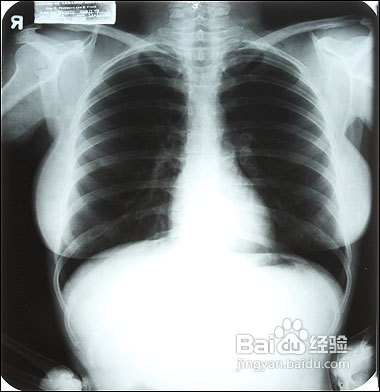

2、内科检査:着重检査心肺听、叩诊、肝、脾和腹部触诊,进行血、尿、便、肝功能化验和X线胸透。